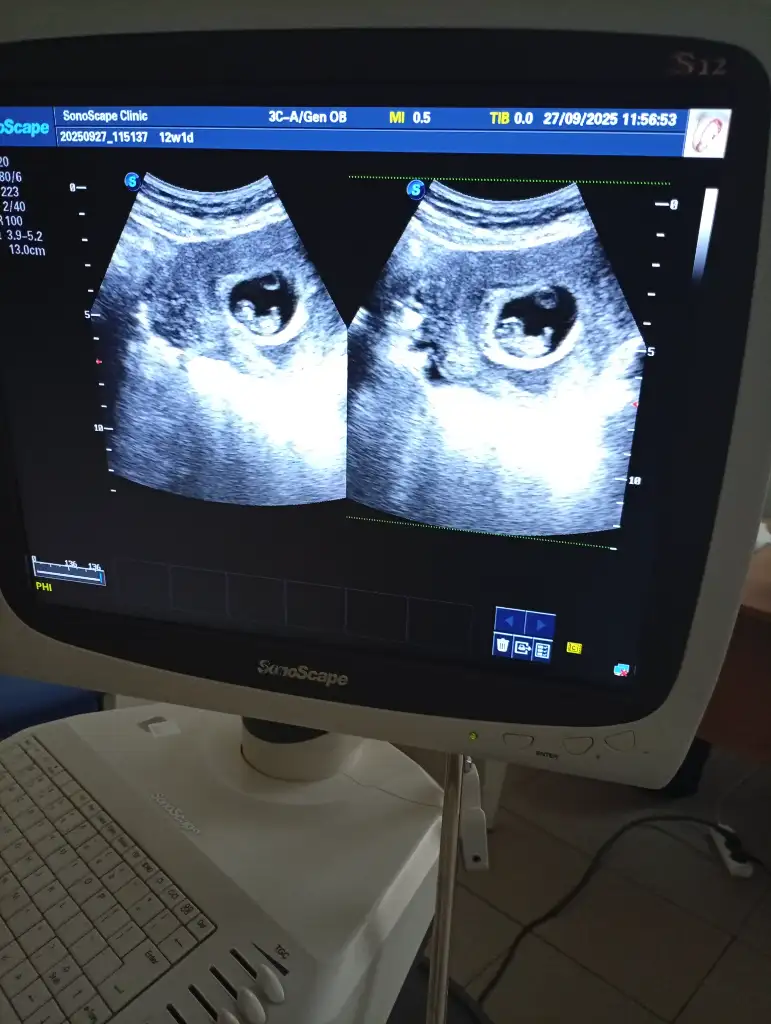

Nub veya Ramzi Theorisi anlayan var mı?

Öncelikle hayırlı olsun. Nub için çok küçük . Ramzi teorisi içinse kız olabilir. Çok bildiğim bir şey değil 😊 hayırlısı olsun

Konu çok ilgimi çekti acaba bakabilir misiniz 🥲 10.hafta

Ramzi teorisi için daha küçük haftalardaki yani bebeğin kese içindeki yerleşimine göre bakıyorlar diye biliyorum. 7 ,8 haftalar gibi.

Burda ise eğer gördüğüm nub ise kız bebek tahminim. Gönlünüzce olur umarım 🙏